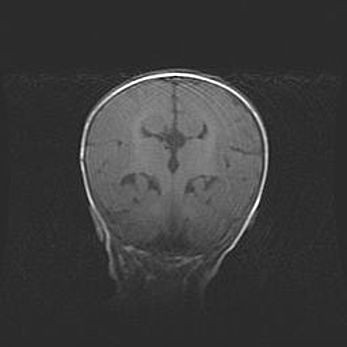

Церебральная ишемия II.

Возраст: 5 дней

Вес: 3400 г

Пол: женский

Окружность головы: 35 см

Срок гестации: 39 недель

Церебральная ишемия – это заболевание, характеризующееся недостаточностью (гипоксией) либо полным прекращением (аноксией) снабжения мозга кислородом по причине закупорки одного или нескольких сосудов. Это приводит к  что метаболическим расстройствам различной степени тяжести в тканях головного мозга, развитию коагуляционных некрозов и гибели нейронов.